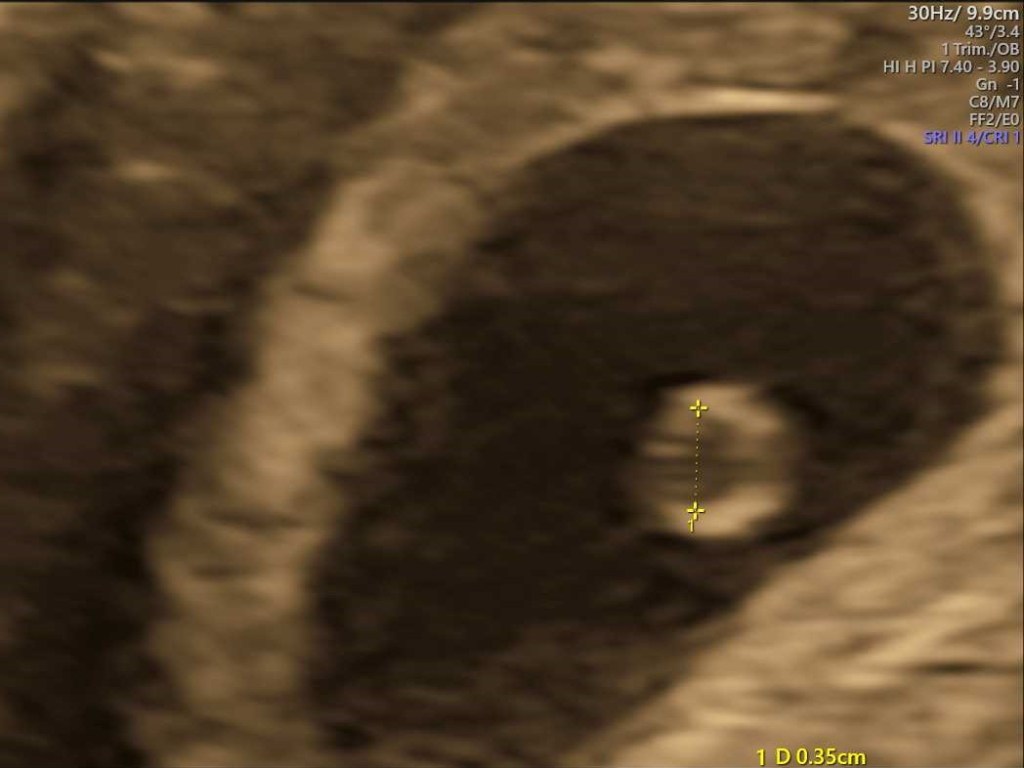

Ultrasound was booked in for Tuesday, which was week 7, day 2, so very early days. Technically a dating ultrasound, but given we knew the conception date, this was to measure and make sure everything was looking good.

I got to see a tiny dot, I guess. There wasn’t much to it. But it was there. I didn’t get to hear a heartbeat, too early for that, but we got to see it, and they could measure it – 146 beats per minute, very good heartrate. And the CRL (which I have just learnt is the “Crown to Rump” measurement) was 1.10cm. Tiny! But it was something.

I know it was still early days, and anything could happen at this stage, but to know there was something there was very cool. And to get some photos for my records.